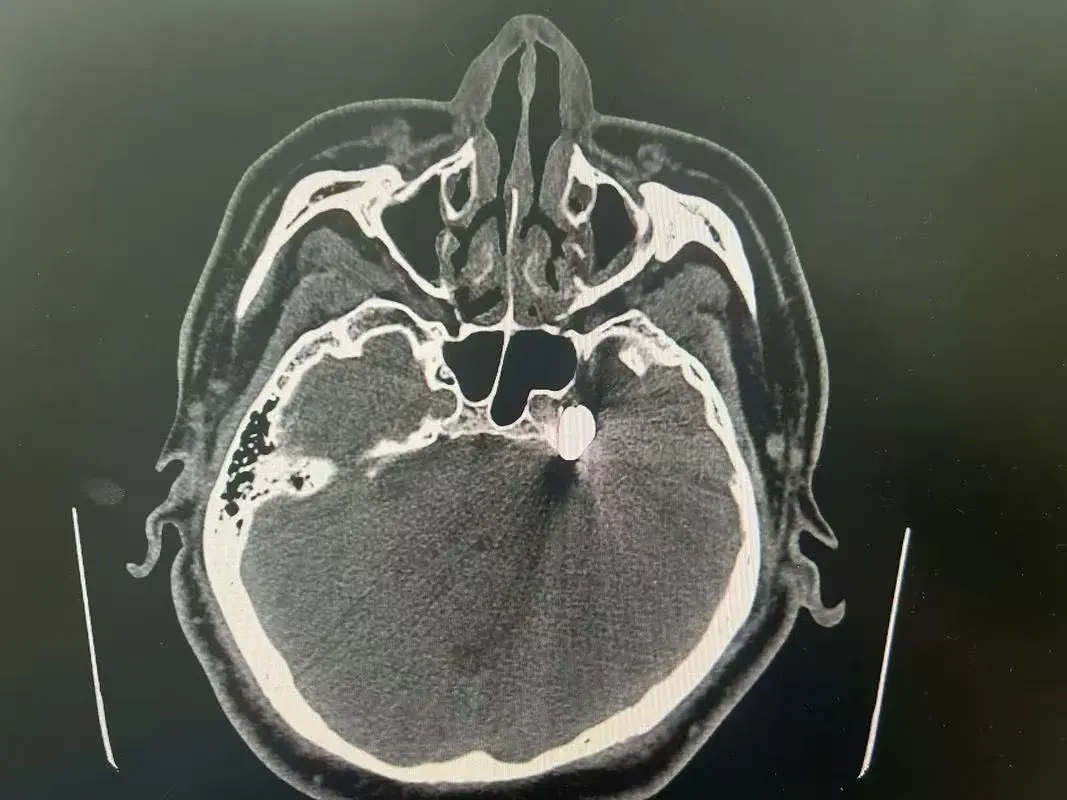

为求彻底解决,家人带她来到市一医就诊。神经外科团队为其完善三叉神经MRI检查,结果提示其右侧三叉神经脑池段小血管紧邻骑跨,这正是反复触发剧痛的“元凶”。患者76岁,合并高血压、房性期前收缩、频发性室性期前收缩等基础疾病,药物治疗效果也不佳,手术是唯一出路,但高龄与基础病让这条路并不平坦。